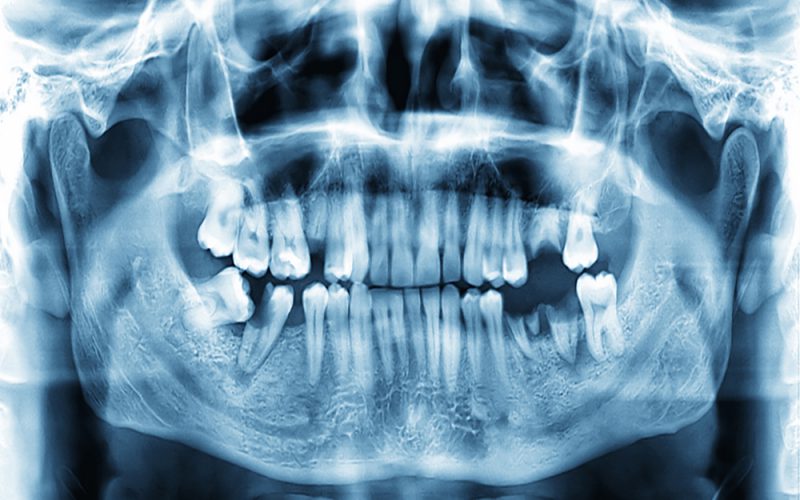

Zdjęcie panoramiczne (pantomogram)

Zdjęcie to wykonuje się, aby ocenić ogólny stan uzębienia oraz zobaczyć wszystkie zmiany chorobowe. Obejmuje ono wszystkie zęby, kości szczęki i żuchwy, stawy skroniowo-żuchwowe oraz częściowo zatoki szczękowe. Ze względu na swoją szczegółowość, wykonywane jest jako podstawowe przed wizytą u specjalisty w dziedzinie chirurgii stomatologicznej, periodontologii, protetyce i ortodoncji.

W naszej klinice zdjęcie pantomograficzne wykonujemy za pomocą pantomografu cyfrowego zewnątrzustnego, w pozycji stojącej. Dzięki temu, mamy bezpośredni wgląd w zdjęcie na komputerze, a pacjentowi gwarantujemy minimalną dawkę promieniowania w porównaniu do metody tradycyjnej.